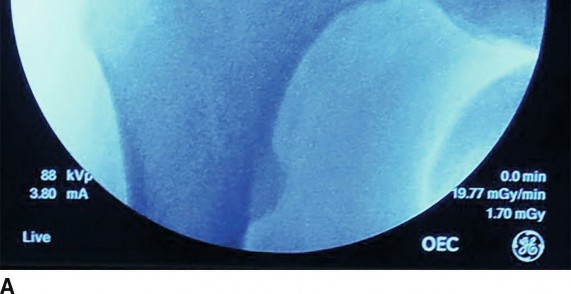

- C-arm Positioning: The C-arm is brought into the sterile field from the contralateral side of the operative hip, positioned to allow unobstructed AP, lateral, and oblique fluoroscopic views throughout the procedure. Initial images confirm patient alignment.

- Traction Application:

- Traction is applied gradually and continuously until adequate distraction of the femoral head from the acetabulum is achieved. This is verified under fluoroscopy, aiming for 8-12 mm of joint space distraction. The amount of traction required varies by patient body habitus, muscle relaxation, and chronicity of joint pathology.

- Verification of Distraction: Under fluoroscopy, confirm adequate joint distraction (8-12 mm of articular space between the femoral head and acetabulum). A neutral rotation of the operative limb is generally maintained for initial portal placement.

- Dynamic fluoroscopy (flexion/internal rotation) is used to confirm adequate resection and freedom from impingement.

- Dynamic Impingement Test: Perform a final dynamic impingement test under fluoroscopy with the hip in flexion and internal rotation to ensure complete resolution of FAI.